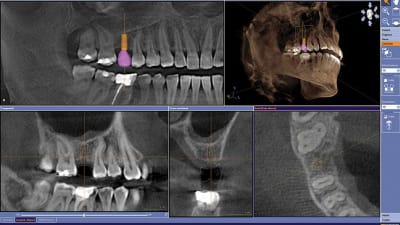

Case Reports General Dentistry Prosthodontics Implants Case Studies CAD | CAM Equipment Case Involving CAD/CAM-Generated, Screw-Retained Bridge Demonstrates Dentistry’s Scientific Progression By Joseph L. Caruso, DDS, Luke S. Khang, CDT September 01, 2012 8 min read